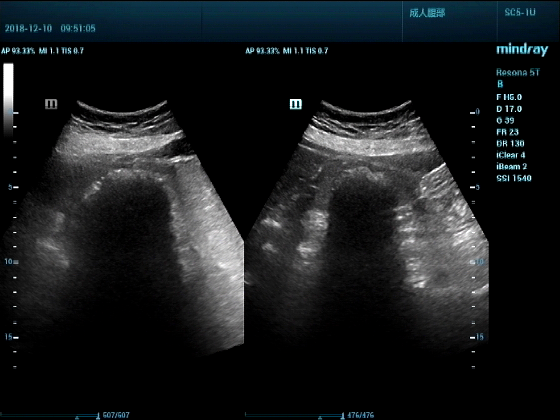

病例一:女,53岁,胃部不适一周来诊

超声可见:胃腔内见一小鸡蛋大强回声团块,后方伴强声影,位置活动。

问及病史吃山楂,柿子。

超声提示:结合临床考虑胃结石,治疗后复查

女,53岁,胃部不适一周来诊